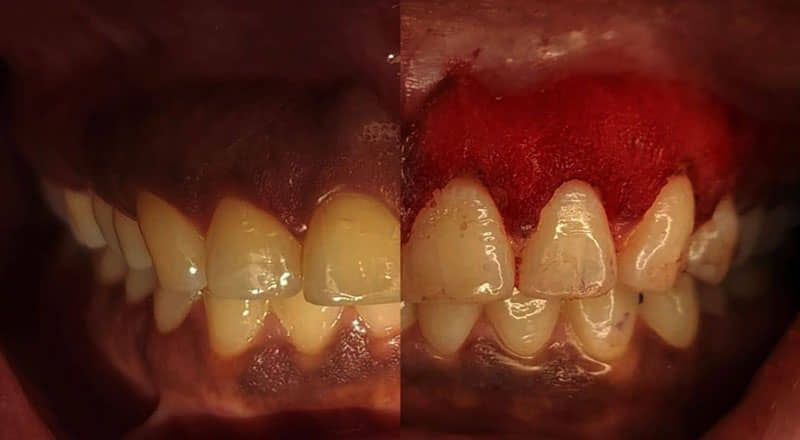

Los signos de alerta incluyen mal aliento persistente, sensibilidad dental, encías enrojecidas o sangrantes. Ignorar estos síntomas puede llevar a complicaciones graves, incluyendo la pérdida de dientes y problemas de salud sistémicos.

Tratamientos efectivos para combatir la periodontitis

En BIOART, ofrecemos una variedad de tratamientos para combatir la periodontitis. Nuestro equipo de expertos diseñará un plan de tratamiento personalizado para tus necesidades.